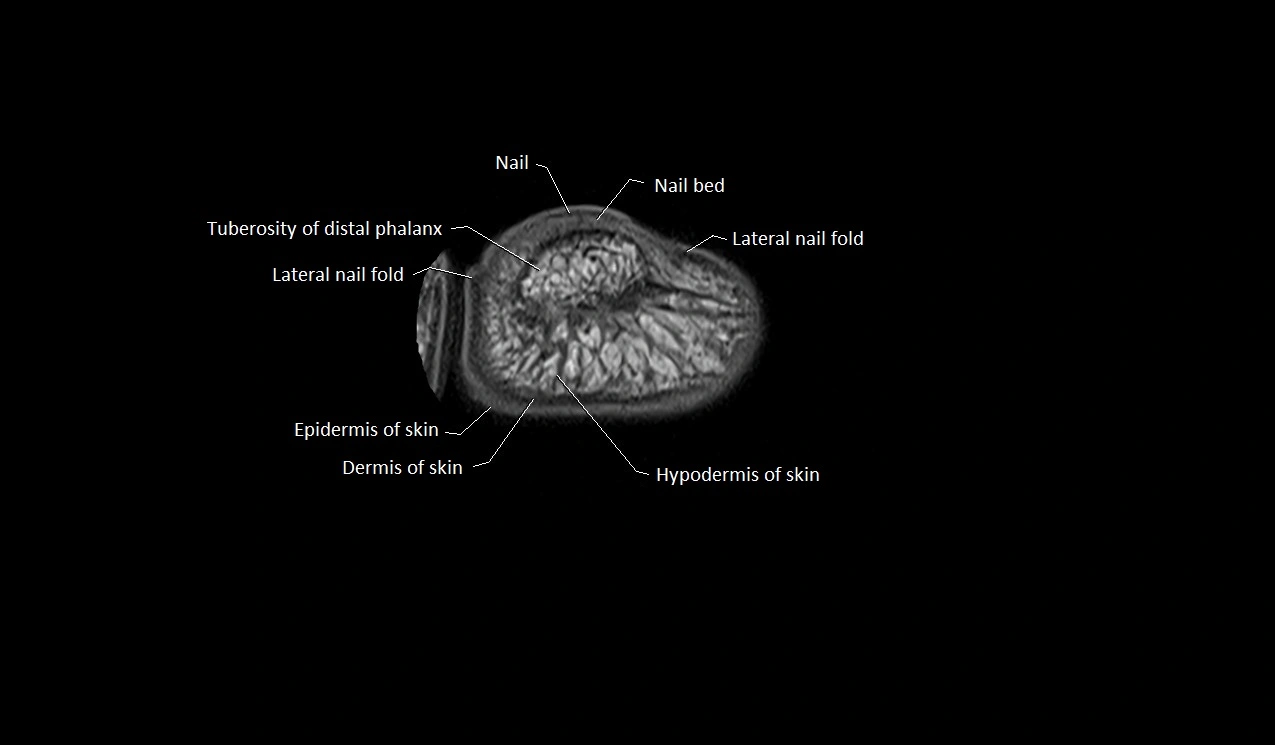

MRI image

image